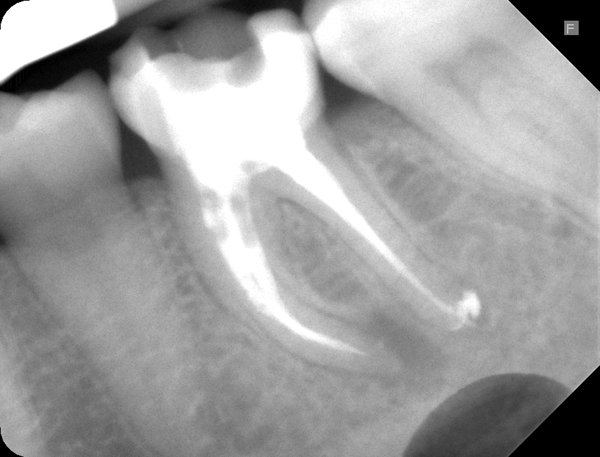

Patientin kam mit einer abgebrochenen Zahnwand in die Sprechstunde. Die Wurzelfüllungen des Zahnes waren insuffizient und wurden revidiert.

Ausgangsröntgen: